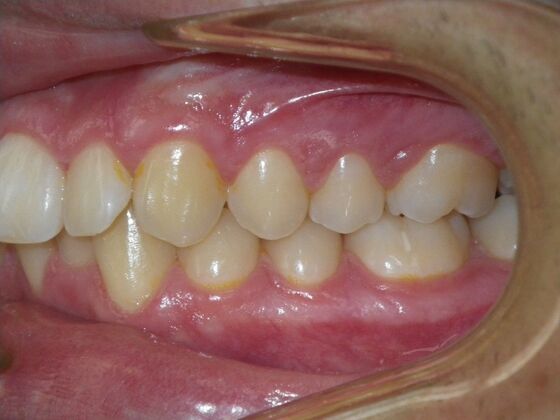

Patient presents with constricted upper and lower arches that will need expansion as well as slenderizing (IPR) to correct upper and lower anterior crowding.